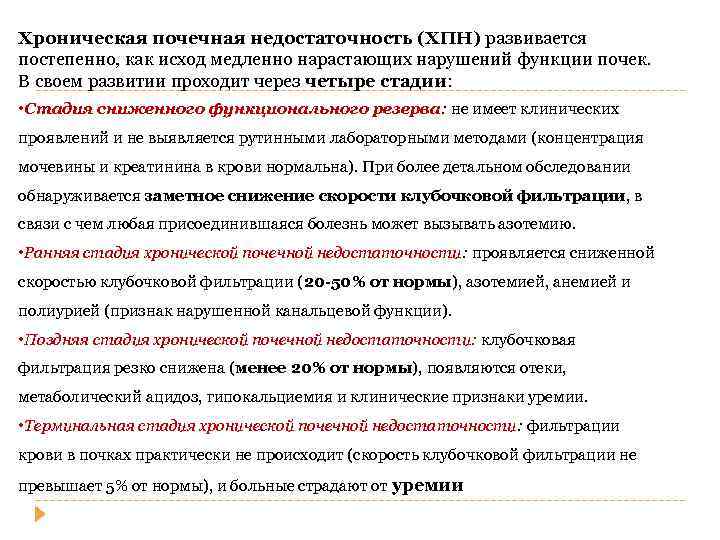

Хроническая почечная недостаточность (ХПН) развивается постепенно, как исход медленно нарастающих нарушений функции почек. В своем развитии проходит через четыре стадии: • Стадия сниженного функционального резерва: не имеет клинических проявлений и не выявляется рутинными лабораторными методами (концентрация мочевины и креатинина в крови нормальна). При более детальном обследовании обнаруживается заметное снижение скорости клубочковой фильтрации, в связи с чем любая присоединившаяся болезнь может вызывать азотемию. • Ранняя стадия хронической почечной недостаточности: проявляется сниженной скоростью клубочковой фильтрации (20 -50% от нормы), азотемией, анемией и полиурией (признак нарушенной канальцевой функции). • Поздняя стадия хронической почечной недостаточности: клубочковая фильтрация резко снижена (менее 20% от нормы), появляются отеки, метаболический ацидоз, гипокальциемия и клинические признаки уремии. • Терминальная стадия хронической почечной недостаточности: фильтрации крови в почках практически не происходит (скорость клубочковой фильтрации не превышает 5% от нормы), и больные страдают от уремии